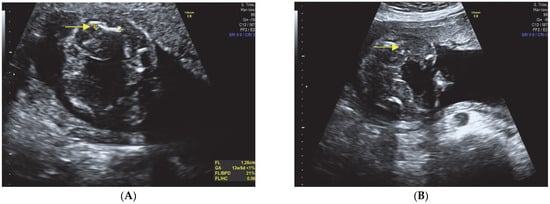

:- Short limbs with severe micromelia affecting all four limbs.

- Remarkably bowed femur and humerus.

- Bilateral clubfoot.